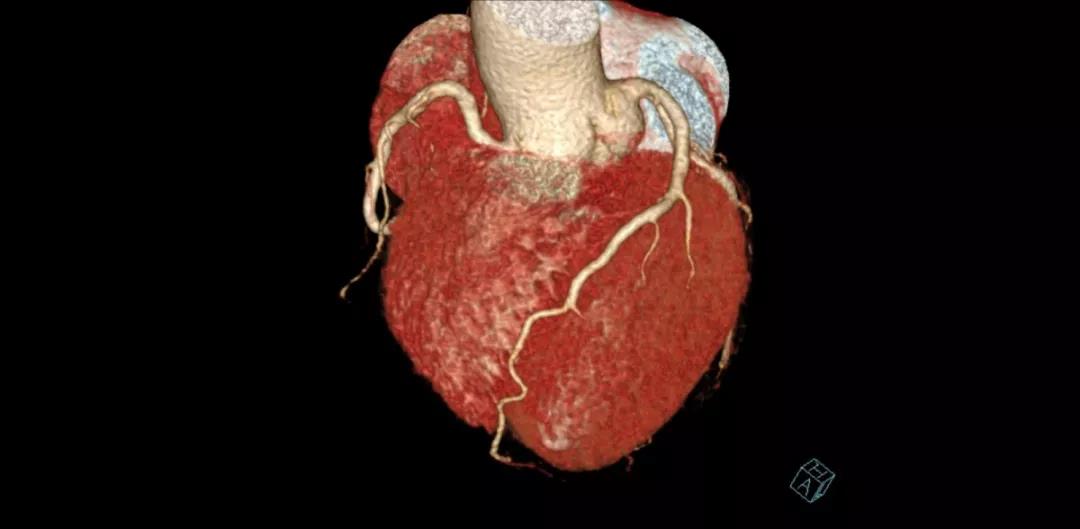

案例圖

冠狀動脈CTA

?具有成像速度快、輻射劑量低、時間分辨率高以及雙能量能譜成像的優(yōu)勢。

?尤其適合心臟及大血管成像、胸部低劑量篩查、痛風石成像等檢查。

?無需控制心率:極限狀態(tài)下心臟掃描僅需0.25秒。

?綠色準確:雙源兩套128層數(shù)據(jù)采集系統(tǒng),提升了圖像質量及診斷正確率;輻射劑量大幅度降低,只需小于1mSv的輻射劑量即可完成心臟掃描;